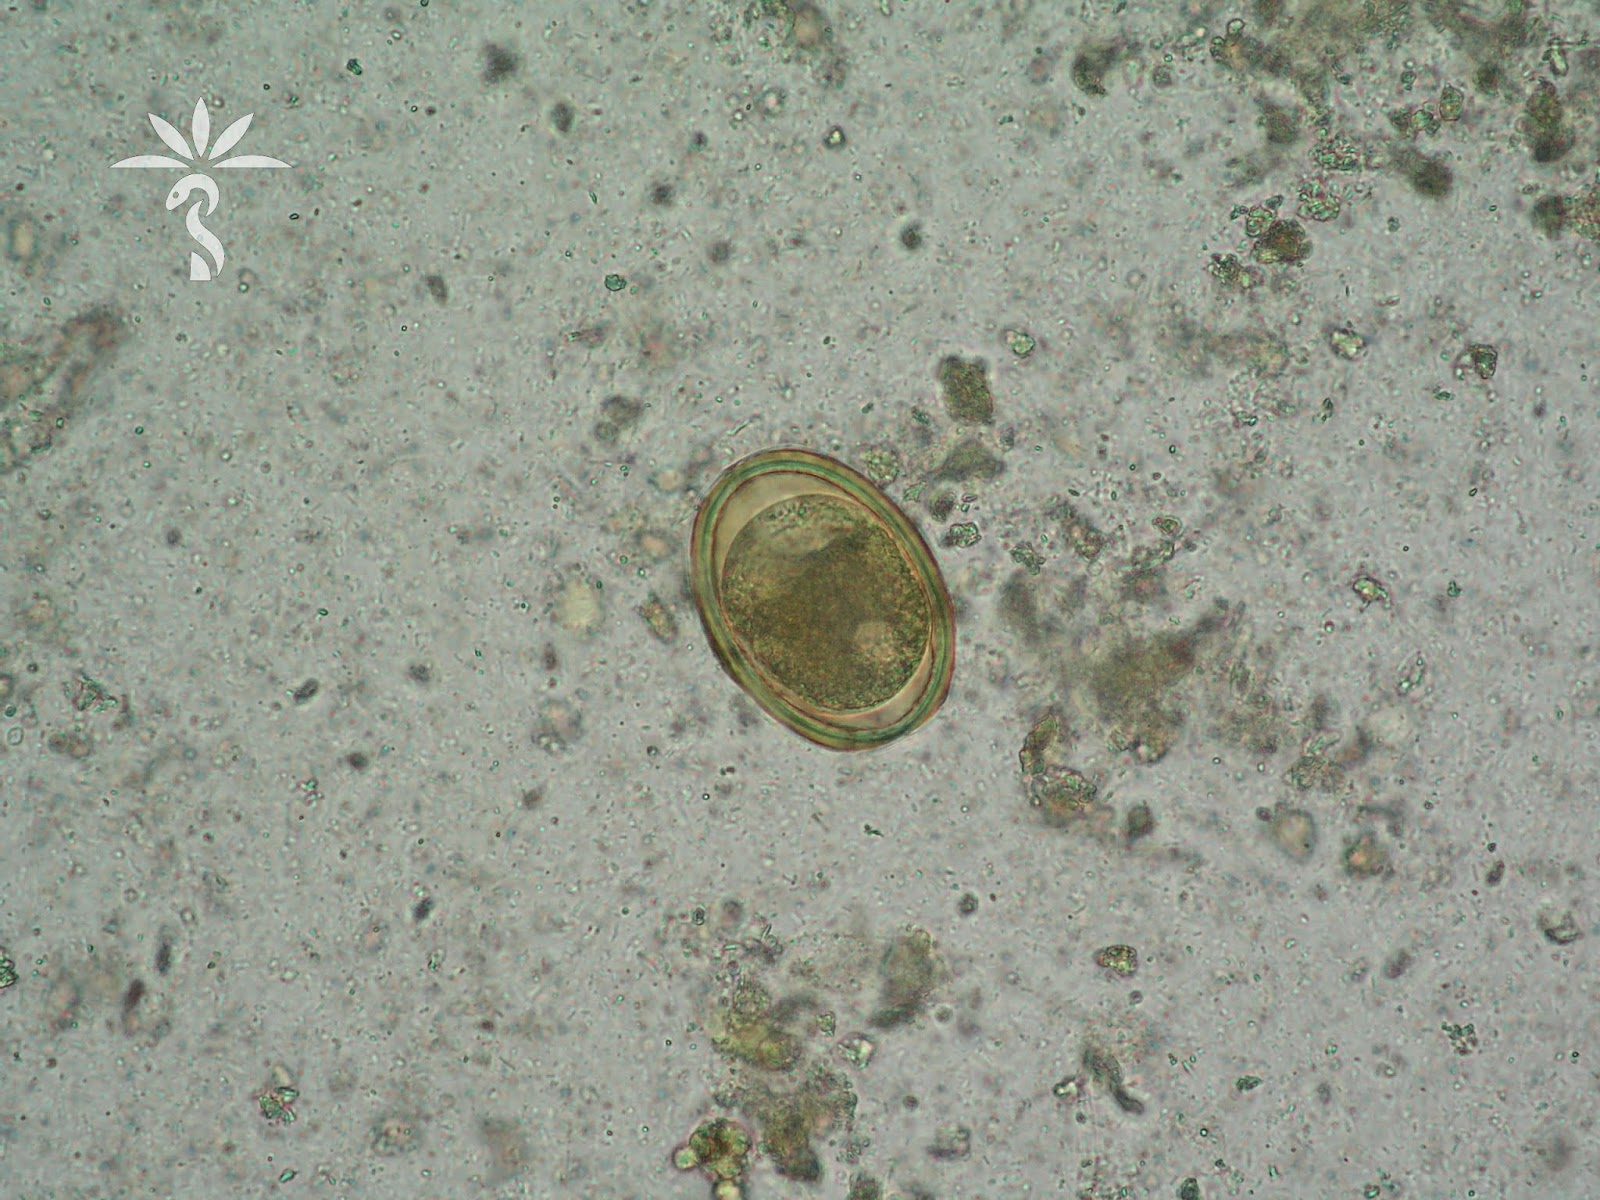

Cdc Dpdx Ascariasis

Ascariasis Image Library Page 3